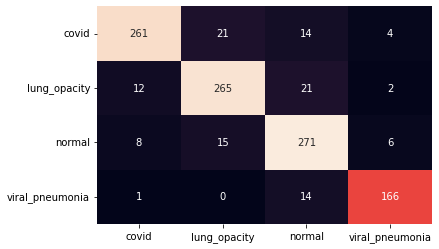

III.2 Classification results

The training procedure in all scenarios has converged. Looking at the evolution of training and validation accuracy (Fig. 11a) indicates that a larger validation dataset would be beneficial. To stabilise the classifier training a procedure of multiple training runs to select the best model is used (Materials and methods). Resulting classifiers are able to discriminate between classes with good precision, for example, see the confusion matrix of the best overall model presented in Fig. 11b. It can also be seen that for the normal class, the rate of misclassified images as COVID-19 ones is higher than for other classes. This effect is present for all models although smaller for the ones based on the EfficientNet-B0 architecture. In addition, the EfficientNet-B0 variants excel if the correct classification of viral pneumonia class images with the smallest rate of errors. However, the EfficientNet-B0 GAN augmentation scenario shows increased misclassification of healthy images which leads to a poor performance. The evolution of the training accuracy as well as confusion matrices for all models are summarised at the end of this section.

Training results for the two architectures are summarised in Figs. 13, 14, 15, 16, and Table 3. For each architecture four scenarios are considered as described in Training process part of the Materials and methods Section.